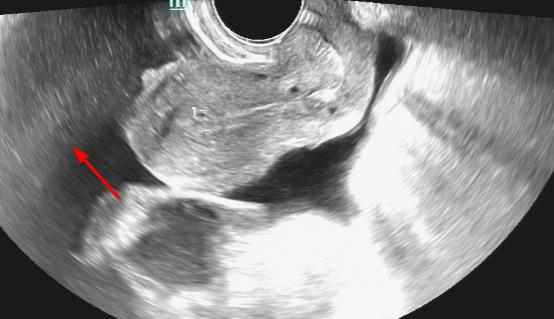

3、盆腔感染

盆腔感染也就是我们所定义的盆腔炎, 盆腔感染的具体表现分为急性盆腔炎与慢性盆腔炎两种, 在盆腔结业诊断的妇科疾病中较为常见。